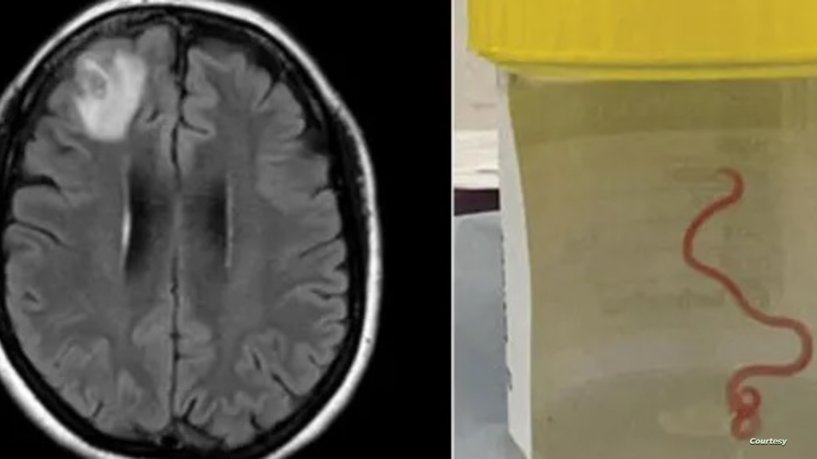

وسحبت جراحة الأعصاب، الدكتورة هاري بريا باندي، الدودة التي يبلغ طولها 8 سنتيمترات من المريضة، مما أصاب العاملين في المستشفى بالدهشة.

وعلى إثر ذلك، أدخلت مستشفى كانبيرا، حيث كشفت فحوص الرنين المغناطيسي لدماغها عن وجود تشوهات تتطلب عملية جراحية.

وخلال العملية، تم الوصول إلى هذا الاكتشاف. وقال طبيب الأمراض المعدية في المستشفى، سانجايا سيناناياكي، إن جراحة الأعصاب لم تتوقع حدوث ذلك، مشيرا إلى أن هذا الأمر “يحدث مرة واحدة في حياتهم المهنية”.

وعقد الفريق الطبي في المستشفى اجتماعا لمعرفة نوع الدودة، لكنهم لم يتمكنوا من تحديد ذلك، وتم إرسالها إلى أحد العلماء المتخصصين الذي أكد أنها دودة Ophidascaris robertsi التي تتواجد في الثعابين.